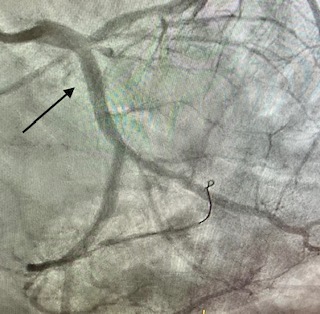

Angioplàstia amb stent en un infart (artèria tancada 100%)